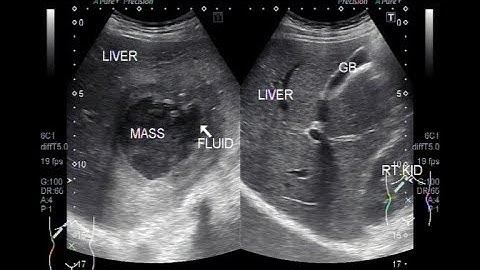

Understanding Pyogenic Liver Abscess Through Ultrasound Imaging